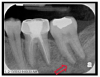

At the September 2011 appointment, significant findings in her intra/extraoral exam consisted of palpable lymph nodes across the left side of the mandible with numbness affecting the lip and chin, tenderness in the region of tooth No. 20, and redness with inflammation that was consistent with gingivitis. To diagnose the etiology of her numbness, a partial full-mouth series of radiographs were taken. No distinguishable carious lesions or apical lesions were noted; however, tooth No. 19 had a stainless steel restoration consistent with a history of endodontic treatment (Figure 1). To rule out other pathologic conditions, an oral pathologist ordered a panoramic image, which was interpreted by a dental radiologist. The radiograph revealed no signs of trauma or other sources to explain the etiology of the numbness. Idiopathic osteosclerosis in the right side of the mandible was present (Figure 2). A prophylaxis was performed and on a 3-week follow-up visit, her gingival tissue health improved but her symptoms still persisted. Recommending she should consult with her oncologist, her treating physician found no evidence of any recurring malignancy.

Fig 2. Panoramic radiograph taken on a follow-up visit exhibiting idiopathic osteosclerosis on the opposing side (noted in red). Idiopathic osteosclerosis noted in red. No pathology for numbness noted for the left side.

Figure 2